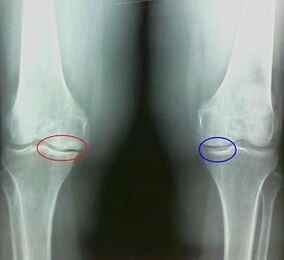

Was ist zum Beispiel der Unterschied zwischen Arthritis und Arthrose des Kniegelenks? Bei Arthritis tritt die synoviale Hülle von Gelenkgeweben auf. Dies führt zu einer Erhöhung der Temperatur im Gelenk.

Das Gelenk schwillt, ein anhaltendes Schmerzsyndrom entwickelt sich und verstärkt sich während der Bewegung. Bei Arthrose treten der Schmerz erst nach körperlicher Aktivität auf, Sie können einen charakteristischen Crunch oder Klicks im Gelenk hören, allmählich ist das Gelenk deformiert und verliert Mobilität.

Arthrose entwickelt sich allmählich und ist in den frühen Stadien nicht merkwürdig. Oft wird es für körperliche Müdigkeit eingenommen. Die chronische Form der Arthrose wird auch als Osteoarthrose bezeichnet. Zur Frage, was schlimmer ist - Arthrose oder Arthrose, ist die Antwort offensichtlich. Die letzte Option ist eine Folge der Entwicklung von Arthrose und ihrer akuten Form.

Unter den Symptomen der Arthrose werden Folgendes unterschieden:

- Nach körperlicher Aktivität treten Schmerzen mit plötzlichen Bewegungen, Kurven, Neigungen, nach Ruhe, Schmerzen;

- Eine charakteristische Krise in den Gelenken ist festgestellt;

- Die Schmerzen nach längerer Ruhe, die innerhalb von 15 bis 20 Minuten nach Mobilität verläuft (dies ist mit den stagnanten Phänomenen verbunden, die im Gelenk auftreten);

- besorgt über Nachtschmerzen, die durch venöse Stagnation auftreten;

- Die entzündliche Form der Pathologie wird von Ödemen und Schmerzen begleitet;

- Die Verbindung ist deformiert, seine Mobilität nimmt ab.